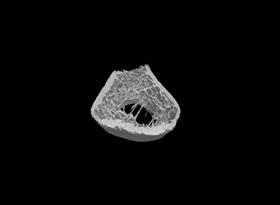

使用MicroCT可以詳細了解牙根管的三維形態(tài),測量根管的高度、體積、截面積、管壁厚度等。